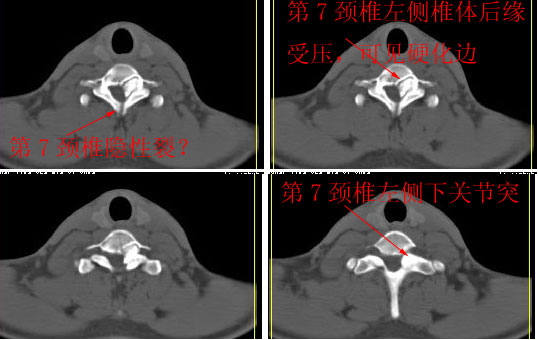

男24岁因一年来感头昏,查体四肢肌力及感觉无异常。颈椎dr未见异常,mri发现c7水平段椎管内左侧占位。患者于7年前有车祸伤病史(但是未检查,自述无异常)。请讨论是否是机化血肿或骨折片,能除外是肿瘤?

ct

椎管内骨性肿块,与第7颈椎左下关节突关系密切,向椎管内生长,第7颈椎椎体左后缘受压变形,边缘可见硬化边,与肿块间间隙清晰。mri扫描肿块内可见骨髓信号,考虑骨软骨瘤可能性大。